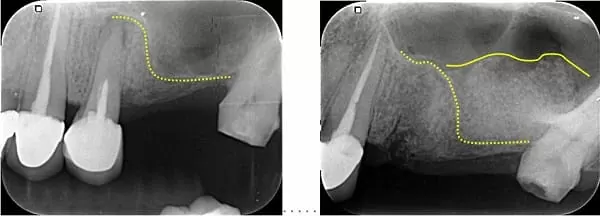

治療前:左上後牙區鼻竇太低、骨量不足 → 治療後:微創補骨增高鼻竇,不腫脹

照射X光片及3D斷層掃描後,確認左上因為缺牙太久,鼻竇氣室化導致骨質流失,幾乎沒有骨頭可以植牙;必須先補骨做鼻竇增高,等待新骨生成後才能植牙。傳統的鼻竇增高手術是一個大手術,通常用側方開窗法施行,患者術後會疼痛而且臉會非常腫脹,非常不舒服。現在科技的進步,已經能用微創法補骨,不僅更安全,而且患者不會腫脹而且低疼痛,讓很多以前不敢做這項手術的人,現在都敢做了!

斷層顯示第一小臼齒外側骨頭已破洞 → 大臼齒區已經沒有骨頭,像蛋殼一樣薄